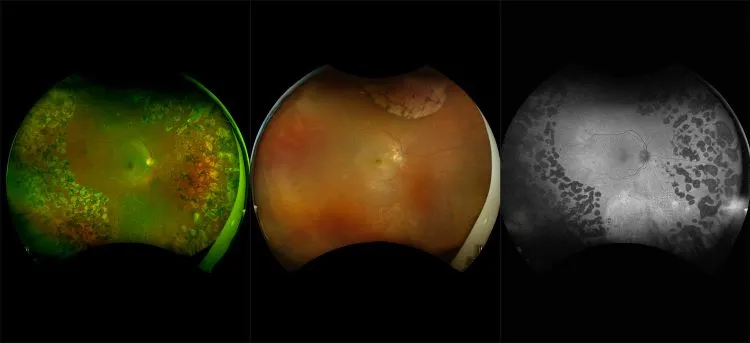

optomap® Recognizing Pathology

This material is designed as a searchable reference resource to support clinical decision-making. The information contained here should be used as general guidance when viewing optomap and OCT images from Optos devices. The differential diagnosis should be made under the direction of the responsible physician. These images were taken on the latest ultra-widefield optomap devices.

The Cases and Images

optomap Recognizing Pathology is searchable by pathology and/or optomap image modality. You may search by multiples of each selection. Each individual case is represented by the accompanying thumbnail image. Most cases include several different optomap image modalities. To view a full description of the case, please click on the thumbnail. Each image in the case will be made available through our OptosAdvance software which provides multi-dimensional visualization of digital images to aid in the analysis of anatomy and pathology. Support and pathology definitions can be found by selecting one of the buttons, above. Should you have questions, please complete the form below.